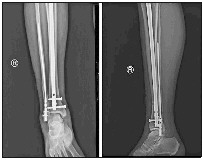

患者亓某,男,48岁,因摔倒致右小腿疼痛活动受限3小时,于3月2日入院,诊为右胫腓骨粉碎性骨折(远段)。

王星主诊医师团队认真分析患者伤情:按常规治疗方法,可采用切开复位胫腓骨远端钢板内固定手术治疗,但小腿远段软组织覆盖少,筋膜间室空间有限,若在胫腓骨外各放置一块钢板,将大大增加筋膜间室的内容物,造成筋膜室高压或刀口缝合困难。通常此类患者术前需等待2周左右,充分消肿后再手术。而且钢板为偏心型固定,力学稳定性远不如髓内钉的中心型固定。王星主诊医师团队经过讨论,决定采取目前最为先进的髌上入路超远端锁定专家级髓内钉固定胫骨,腓骨远端髓内钉固定腓骨的手术方案。由于腓骨髓内钉省内鲜有应用,创伤骨科申请由外省调来腓骨髓内钉器械,于3月10日顺利完成胫腓骨远端2处骨折2种髓内钉固定手术。术后拍片骨折复位固定良好。